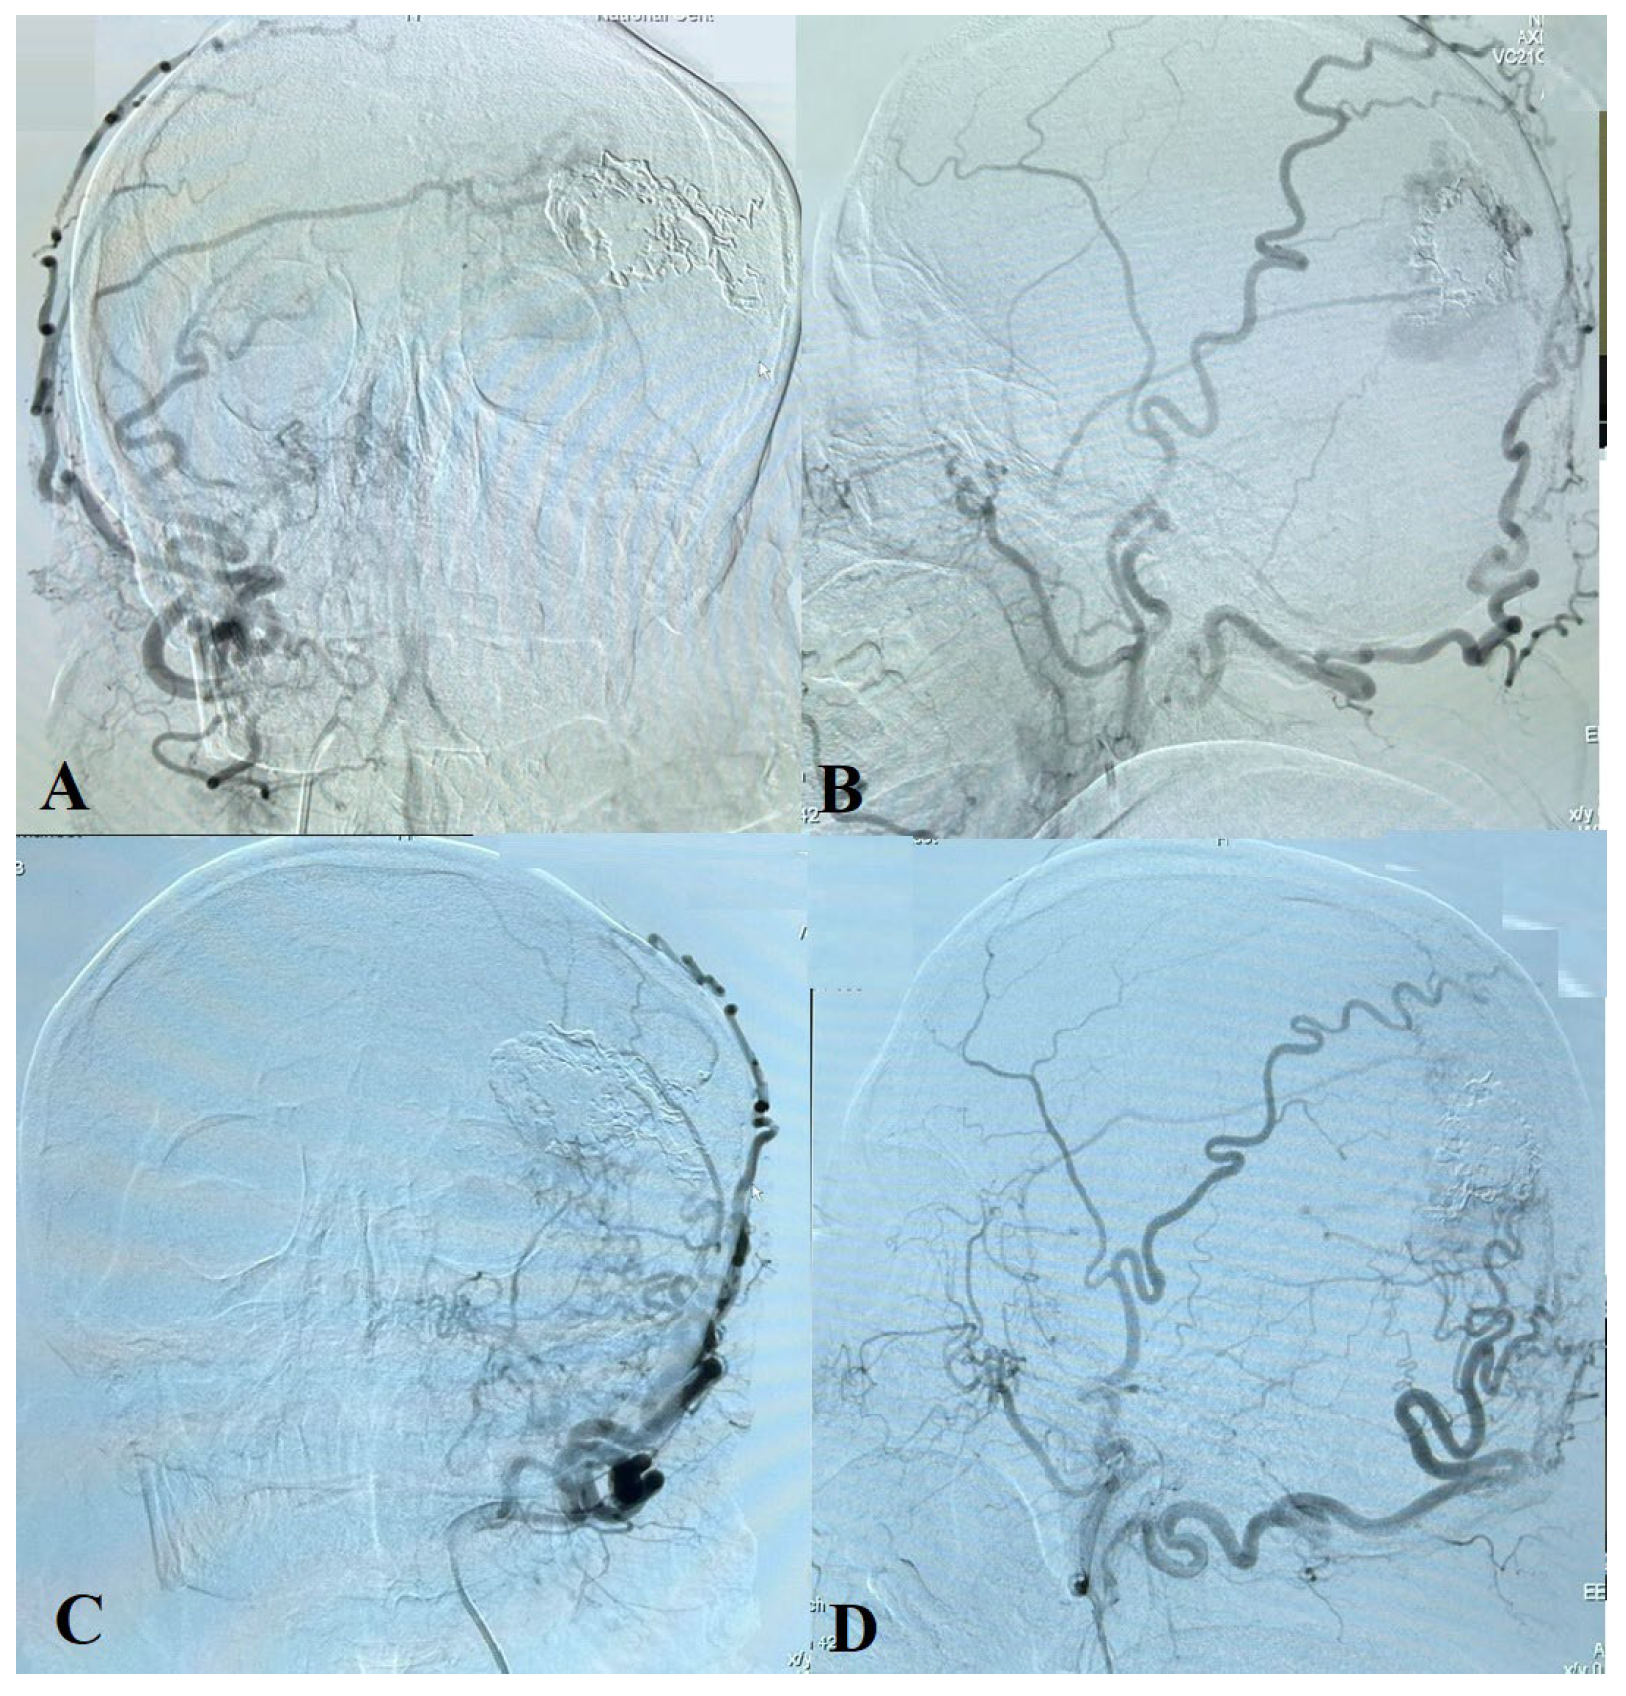

2. Case Presentation

2.1. Diagnostic Procedures

2.2. Treatment